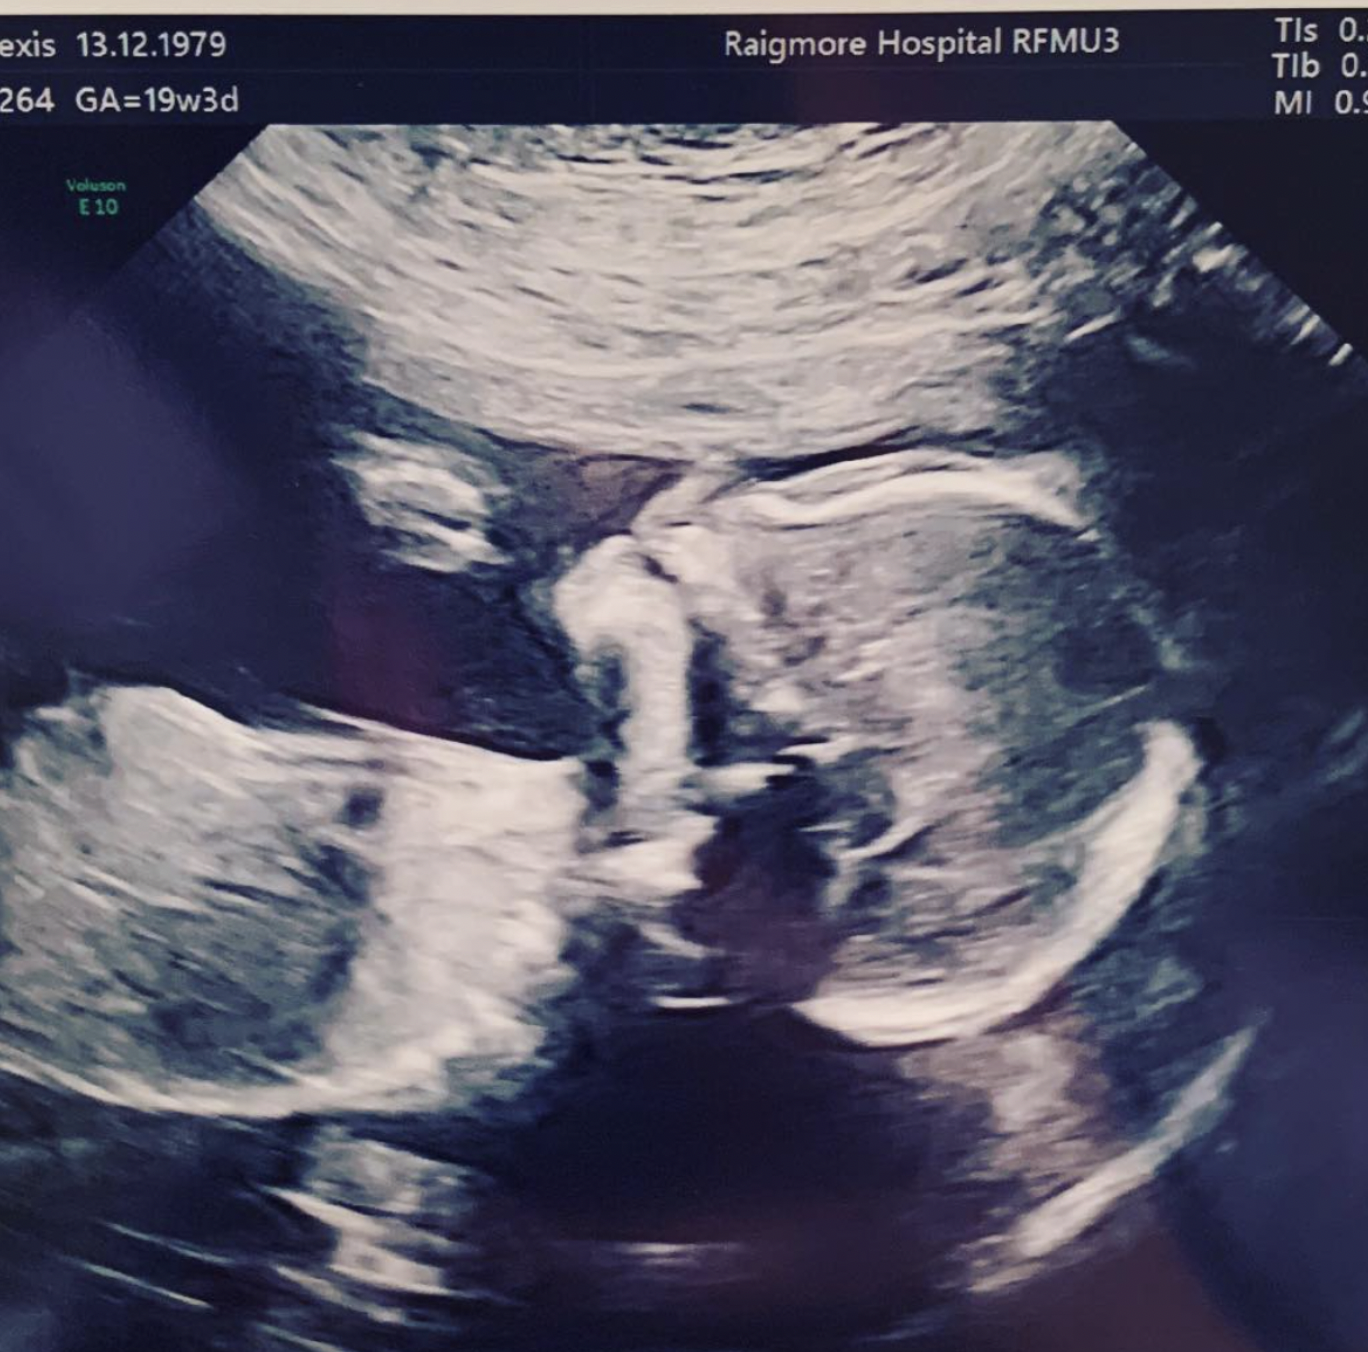

But a couple months later, both she and her husband were shocked when the doctor told them that they were finally expecting a girl.

Of course, there was a 50% chance of the baby being a girl. But the parents had gotten so used to the idea of having sons that they couldn’t come to terms with the news for a while.